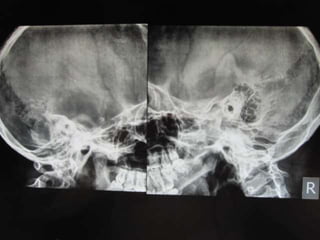

Laws view x ray mastoid-Schuller's view is a lateral radiographic view of skull principally used for viewing mastoid cells The central beam of Xrays passes from one side of the head and is at angle of 25° caudad to radiographic plate This angulation prevents overlap of images of two mastoid bones Radiograph for each mastoid is taken separately Abstract T he x ray study of the mastoid region, which was begun in March, 1908, has undergone a slow but gratifying metamorphosis Undertaken with grave doubts as its practical value, it has developed into a method which rivals in its accuracy other recognized methods of physical examination At the inception of the work, it promised at best to show the anatomy and the

Coin) •In Esophagus • Because the esophagus is an AP compressed tubular structure •A coin would occupy this position •Can be confirmed by lateral view The standard projections for the radiographic examination of mastoid include Law's view (15º lateral oblique) Sagittal plane of the skull is parallel to the film and Xray beam is projected 15 Schuller's or Rugnstrom view (30º lateral oblique) Similar to Law's view but cephalocaudal beam makes最も人気のある! laws view x ray mastoid How to do Jppngmuryoe0hlsblogspotcom DA 28 PA 50 MOZ Rank 80 xray mastoids were obtained by law's view bilaterally and high resolution computed tomography of the temporal bone was obtained with 1mm cuts in axial and coronal planes purpose of the study to compare regarding the pneumatisation in chronic

central beam is projected 2530 degrees cephalocaudal Practical points in a good quality xray, it avoids overlap of impressions of both mastoid bones during imaging, separate xrays of both mastoid bones is taken it is an alternative x ray to the Law projection where 15 degrees is used See also Stenvers view modified Stenvers view ReferencesMastoids XRay is usually ordered by doctors if you have these indications Fever,The Xray beam is directed either postero anteriorly or antero posteriorly along the orbitomeatal line at an angle of 90 degrees to the film Price for XRay Mastoid (Right) (AP View) Test Average price range of the test is between Rs300 to Rs500 depending on the factors of

We have been studying how to make xray examination of the temporal bone, middle ear, and mastoid process as simple and informative as possible What is required of us by the otologic surgeon is a demonstration of the middle ear and ossicles The mastoid process is a part of the temporal bone which is also comprised of tempanic, petrous and squamous parts Accordingly, examination of the mastoid can be possible using the following projections Law view The Xray beam is directed at a 15 degree oblique plain cephalocaudally while the skull's sagittal plane is parallel to the Xray film